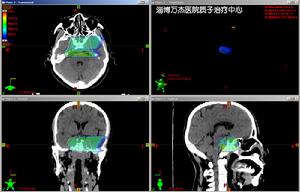

腦部脊索瘤質子治療計畫3、質子照射技術

脊索瘤增殖緩慢,而且瘤體毗鄰重要機構如視神經、視交叉、腦幹等,因此保證瘤體得到較高劑量的照射、周圍重要結構處於相對安全的劑量,高線性能量傳遞放療設備如質子束有其套用價值。使用質子束進行照射有兩種方式,一種為單一質子照射,另外一種為質子與光子的混合照射。目前在臨床上多採用後一種治療方式。

在質子和光子的混合照射種,一般光子與質子的劑量比為4:1~2,有以下兩種混合方式:a、常規分割照射過程中,光子每周照射4次,第5次照射採用質子照射。如此,在總量

腦部脊索瘤質子治療計畫60CGE的前提下,光子照射的總量為50GY,而質子照射的總劑量為10CGE。b、先行光子照射40GY,然後採用質子束局部加量照射20CGE,使總量達到60CGE